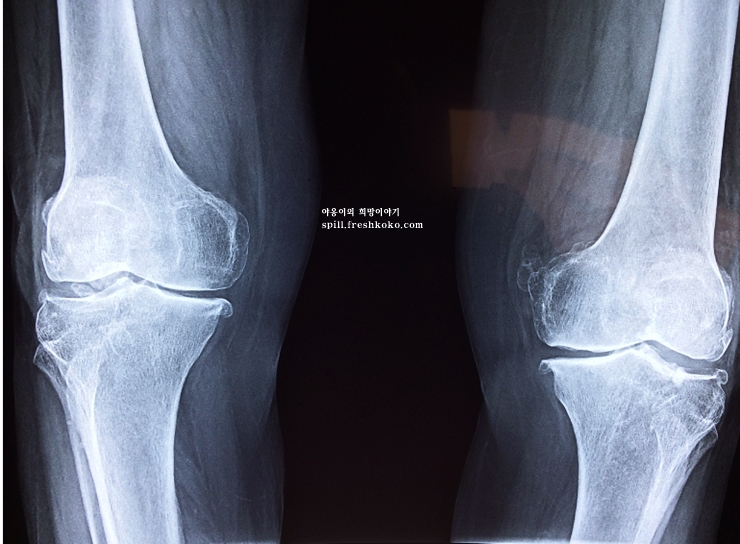

흐르는 세월에 의해 우리의 연골도 점차 닳으면 뼈 표면이 노출되고 노출된 뼈는 걸을 때마다 삐그덕 삐그덕 되면서 통증이 발생됩니다. .이러한 상황이 지속되면 퇴행성 관절염으로 연결 됩니다. 연골은 노화 뿐만 아니라 외상에 의해서도 손상 될 수 있는 부분이기 때문에 특별한 주의가 필요합니다.

무릎 연골이 손상 되면 문제점은 신경세포가 존재하지 않는 곳이기 때문에 손상이 되어도 본인 스스로 별다른 통증을 느끼지 못한다는 것 입니다. 물론 병을 악화시키게 됩니다. 어느정도 오랫동안 증상이 지속되면 연골이 손상돼 무릎 위, 아래 뼈가 맞닿아 통증을 느낄 때 비로소 발병 여부를 파악한다고 합니다.

만약 3개월이상 치료를 받았는데도 통증이 완화되지 않는다면 이는 무릎 골관절염 환자일 수 있습니다. 이는 유전자세포치료제를 활용하여 통증을 개선하고 관절염이 악화되는것을 억제할 수 있겠습니다.